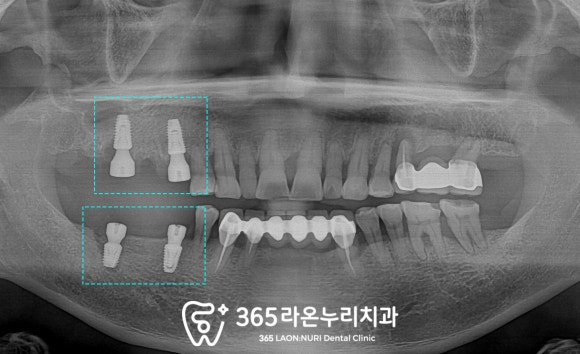

■ 2. 엑스레이 진단

남촌동 치과 에서는

전반적인 상황을 알기 위하여

파노라마 엑스레이를 찍어보았는데요,

보이는 것처럼 이가 없는 곳은

텅 비어있는 게 보이고

치조골의 높이도 낮아진 부위가 있습니다.

파노라마보다 조금 더 가까이서

높은 해상도로 볼 수 있는

치근단 사진을 찍어보니

오른쪽 위 내려간 잇몸뼈의 높이가

더욱 확실히 보이네요.

비어있는 오른쪽 아래 구치부도

마찬가지로 살펴보았는데요,

맨 뒤에 임플란트를 심어둔 곳에

염증이 생겨 주변으로 뼈가 녹아있습니다.

왼쪽 위아래도

전반적으로 뿌리 끝 염증이 심하시고

뼈가 많이 내려가신 상태로 판단됩니다.

이렇게 치아를 잡아주는

치주조직이 좋지 못하니

당연히 이가 흔들리고

저작하기에 힘든 부분이 있으셨겠네요.